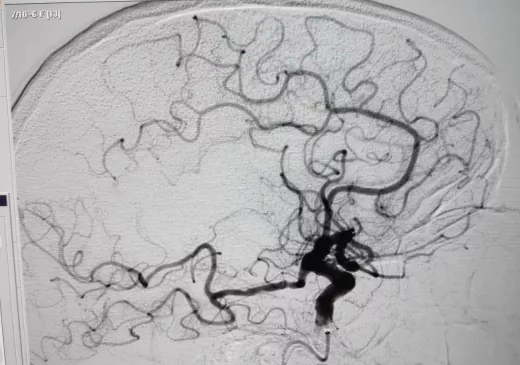

La sala de radiologia intervencionista durant la realització d'una trombectomia mecànica a un pacient que havia patit un ictus isquèmic.

En aquestes dues imatges, podem veure com queda afectada la circulació arterial arran d'un ictis isquèmic i com es recupera després del tractament endovascular.